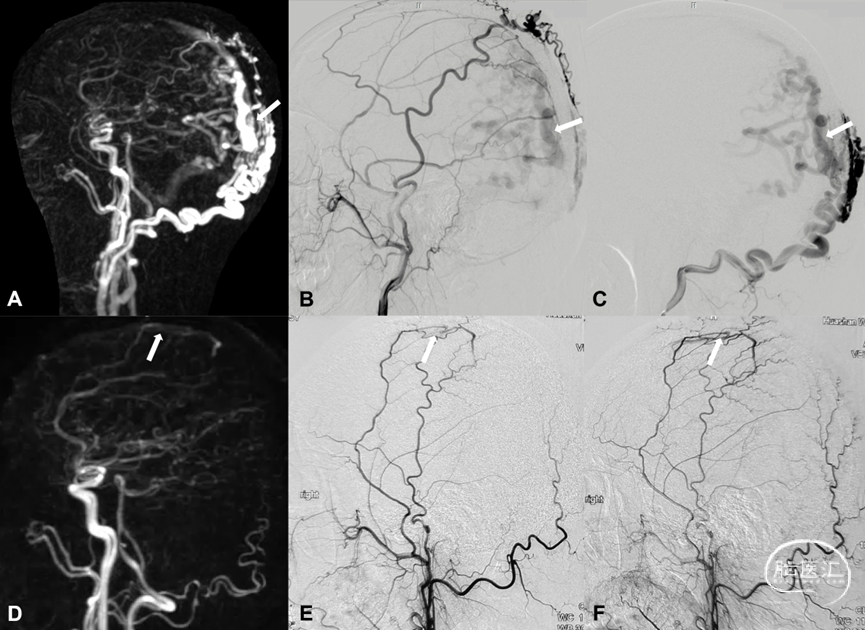

TOF-MRA是筛查和诊断DAVF并对DAVF进行分区定位的常用方法。DAVF的形态学特征包括供血动脉特点、瘘口部位、颅内静脉血栓形成等情况。识别DAVF血管构筑特点对于指导临床治疗具有非常重要的实用价值。有研究报道称TOF-MRA诊断DAVF的敏感性高达79.49% (95%置信区间CI: 66.81%–92.16%) ,特异性达100% (95%置信区间CI: 100.00%–100.00%) ,其主要诊断效力在于识别责任动脉及引流静脉。TOF-MRA原始图像具有较高的空间分辨率,对DAVF的关注点主要集中在瘘口复合体的基本形态,主要包括供血动脉、引流静脉、共同静脉端及逆流皮层静脉。

图7. 右侧枕动脉 (Occipital artery, OA) 参与DAVF供血,轴位最大信号投影 (Maximum intensity projection, MIP) 图发现右侧OA (箭头示) 较左侧OA (细箭示) 直径增宽、信号明显增强 (A) ;3D TOF血管重建,剪除周围血管后可以清晰显示右侧OA明显增粗 (B箭头示) ;右侧枕动脉造影证实右侧OA参与DAVF供血 (C箭头示)。左侧脑膜垂体干 (Meningo-hypophyseal trunk, MHT) 参与DAVF供血,轴位MIP图发现左侧MHT直径明显增宽、信号明显增强 (D箭头示) ;3D TOF血管重建清晰显示左侧MHT明显增粗 (E箭头示) 。左侧颈内动脉造影证实左侧MHT参与DAVF供血 (F箭头示) 。右侧脑膜后动脉 (Posterior meningeal artery, PMA) 参与DAVF供血,轴位MIP图发现右侧PMA直径明显增宽信号增强 (G箭头示) ;3D TOF血管重建显示右侧PMA明显增粗 (H箭头示) 。右侧椎动脉造影证实右侧PMA参与DAVF供血 (I箭头示) 。

图8. 识别共同静脉端。3D TOF-MRA轴位可以识别左侧侧窦区DAVF弥散引流静脉集中向左侧横-乙状窦交界区 (Common collector, 共同静脉端,A箭示) 及窦汇区汇流 (共同静脉端,B箭示) 。DSA造影证实DAVF弥散,向横乙交界区及窦汇区附近汇流 (共同静脉端,C-F箭示) 。